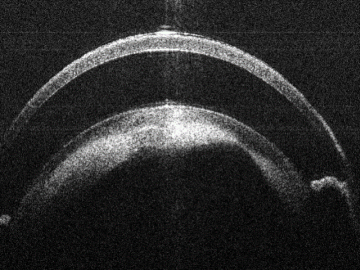

Bioptigen sdOCT Imaging System

Sample Bioptigen sdOCT Imagery:

Anterior Segment